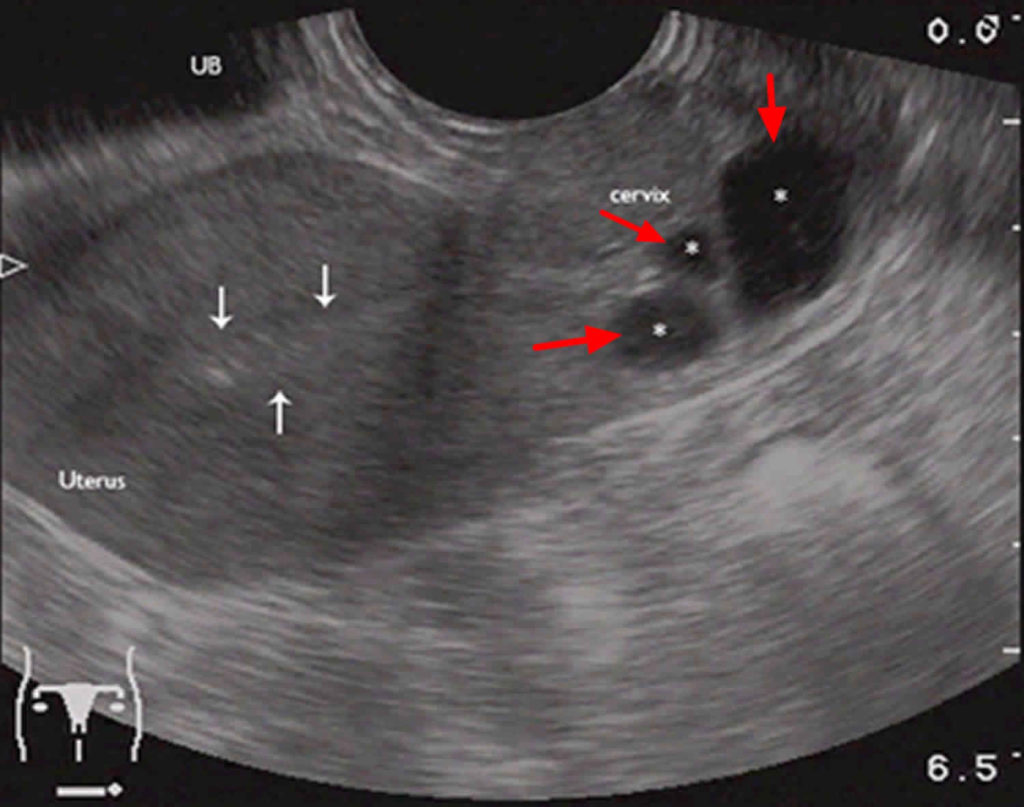

کیست نابوتین که کیست دهانه رحم، کیست احتباس مخاطی یا کیست اپیتلیال نیز نامیده می‌شود، کیست ریزی است که روی سطح دهانه رحم ایجاد می‌شوند. این کیست مملو از مخاطی است که توسط غدد دهانه رحم ترشح می‌شود.

اندازه کیست های نابوتین از چند میلی‌متر تا چهار سانتیمتر متغییر است. این کیست ها صاف هستند و به زنگ سفید یا زرد ظاهر می‌شوند. اما باعث درد، ناراحتی یا علائم دیگر نمی‌شوند؛ بنابراین احتمالا پزشکتان در طول معاینات معمول لگن متوجه بروز یک یا چند کیست در دهانه رحم شما خواهد شد.